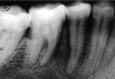

Osteosarcoma is a classical malignant bone-forming neoplasm which usually presents with an aggressive clinical course. The current case is presented with the radiographic feature of widening of the periodontal ligament space of the involved teeth, which is considered to be the earliest radiographic manifestation of osteosarcoma involving the jaw bone. The main aim of this case report was to focus on the importance of early diagnosis of this tumor based on clinical and radiographic examinations, and confirmation by histopathology. Considering the rarity of the disease type and particularly taking into account the fast progression and aggressiveness of this neoplasm, it is clear that the presentation of a clinical case represents a major contribution to better understanding of osteosarcomas involving the jaw bone.